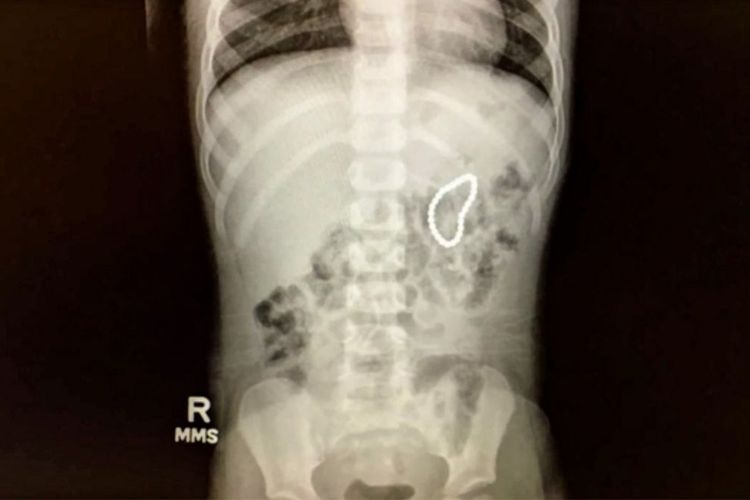

:quality(30):format(webp):focal(0.5x0.5:0.5x0.5)/wow/foto/bank/originals/28-magnet-buckyball-dalam-saluran-cerna-anak-membuatnya-masuk-ugd_20171027_144057.jpg)